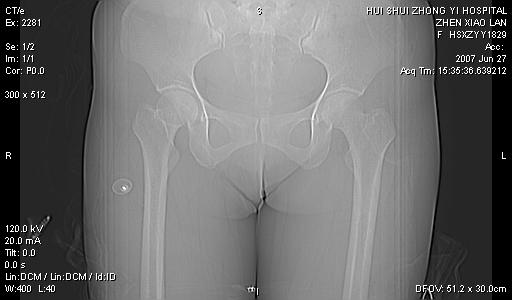

以下是引用还珠格格在2007-6-28 15:15:00的发言:[br]子宫明显增大,偏向盆腔右侧,密度均匀,和子宫同密度, 考虑 子宫肌瘤可能性大 建议增强 除外子宫平滑肌肉瘤。

以下是引用dyqct在2007-6-28 15:41:00的发言:[br]考虑多发子宫肌瘤可能性大,建议进一步增强检查。